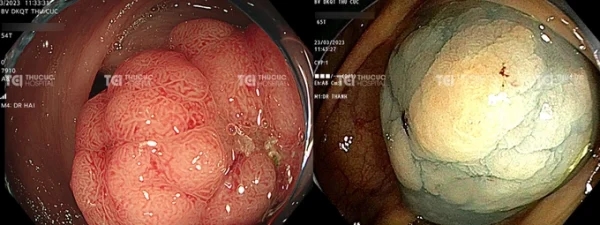

Hình ảnh polyp nghịch sản nặng với kích thước lớn gần như chiếm trọn lòng đại tràng.